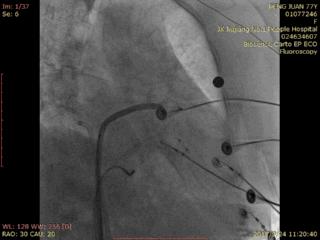

ACP封堵过程:

术中造影:

RAO 30 CAU 20 Fish Ball造影:

RAO 30 CAU 20 牵拉试验: